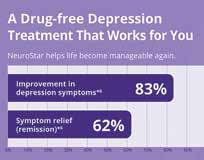

TAP INTO A NEW POSSIBILITY for depression

NeuroStar® Connects. •

NeuroStar is like physical therapy for the brain. It uses magnetic pulses, similar in strength to MRI, to reignite dormant connections in the brain and give you control of your depression. With NeuroStar, you can live on your terms.

Scan here to take a free HIPPA compliant PHQ9 self assessment test.

“When you’re depressed you’re always fighting to live… to survive the next day. NeuroStar made such a difference… all of a sudden I felt empowered, I felt strong, I felt like I wasn’t a victim anymore.” ~DEBBIE